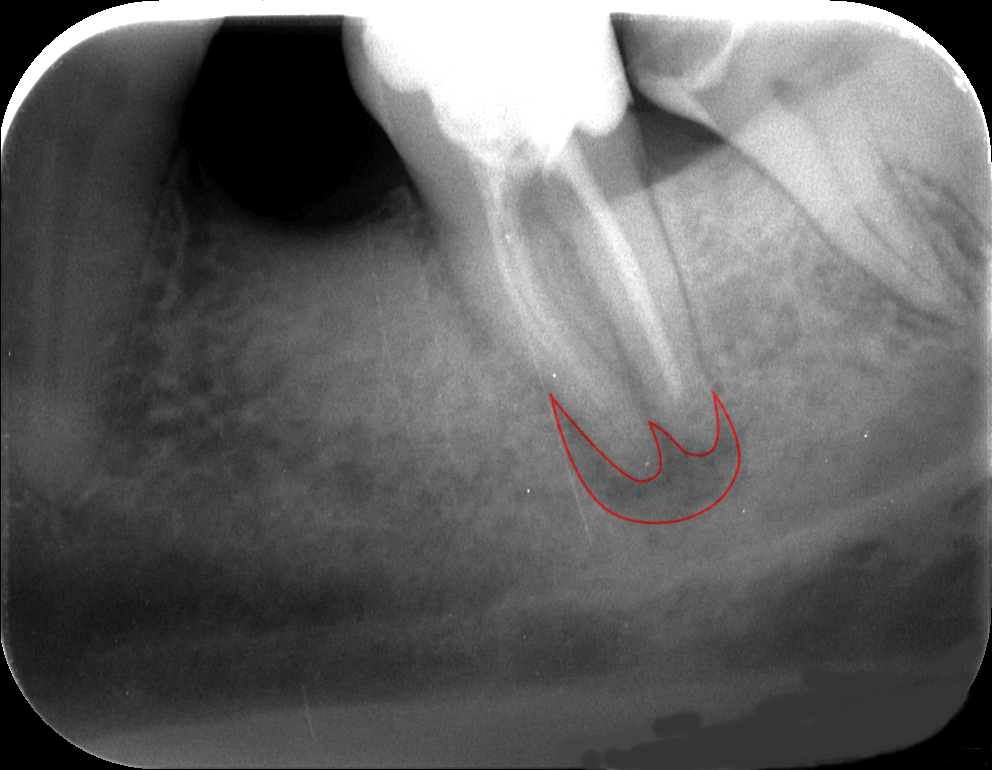

- Gyökércsúcs körüli gyulladás (periapicalis laesio). Azon gyökérkezelt fogaknál, amelyeknél a gyökértömés nem megfelelő vagy a gyökértömés ugyan jónak mondható, de a gyökércsúcs körül krónikus gyulladás alakul ki (granuloma, ciszta, tályog)

Szerencsére a gyulladás jelenlétét a röntgenfelvételek többnyire szépen kimutatják, így fény derülhet a meglétükre – vagy hiányukra.

A krónikus ínygyulladás megszüntetésének első lépése például egy alapos fogkő-eltávolítás (professzionális fogtisztítás). A kialakult ínytasakokat nyitott vagy zárt kürettel kezeli parodontológus szakorvosunk. A nem megfelelő gyökértömés vagy a gyökércsúcs körüli gyulladás megszüntetése esetén a gyökértömés cseréje válhat szükségessé, mely mikroszkópos gyökérkezeléssel orvosolható. Bizonyos esetekben szájsebészeti beavatkozás szükséges pl.: elő nem tört bölcsességfogak, bent maradt gyökerek eltávolításakor, ciszta, illetve tályog kialakulásakor. (Képünk egy altatásban végzett cisztaeltávolításról készült.)